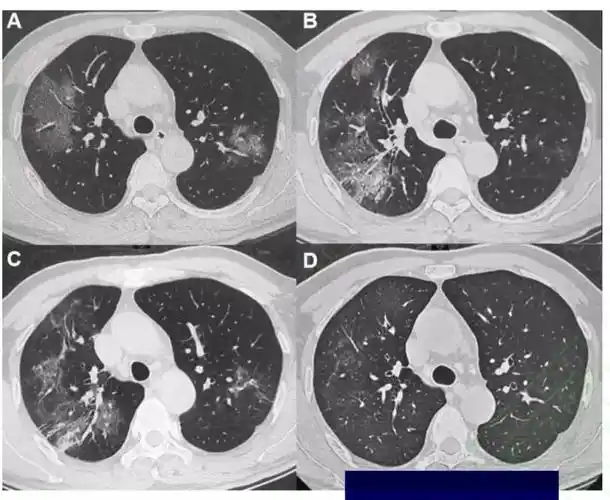

新冠肺炎呈阳性的 ct 扫描图像示例. 方法